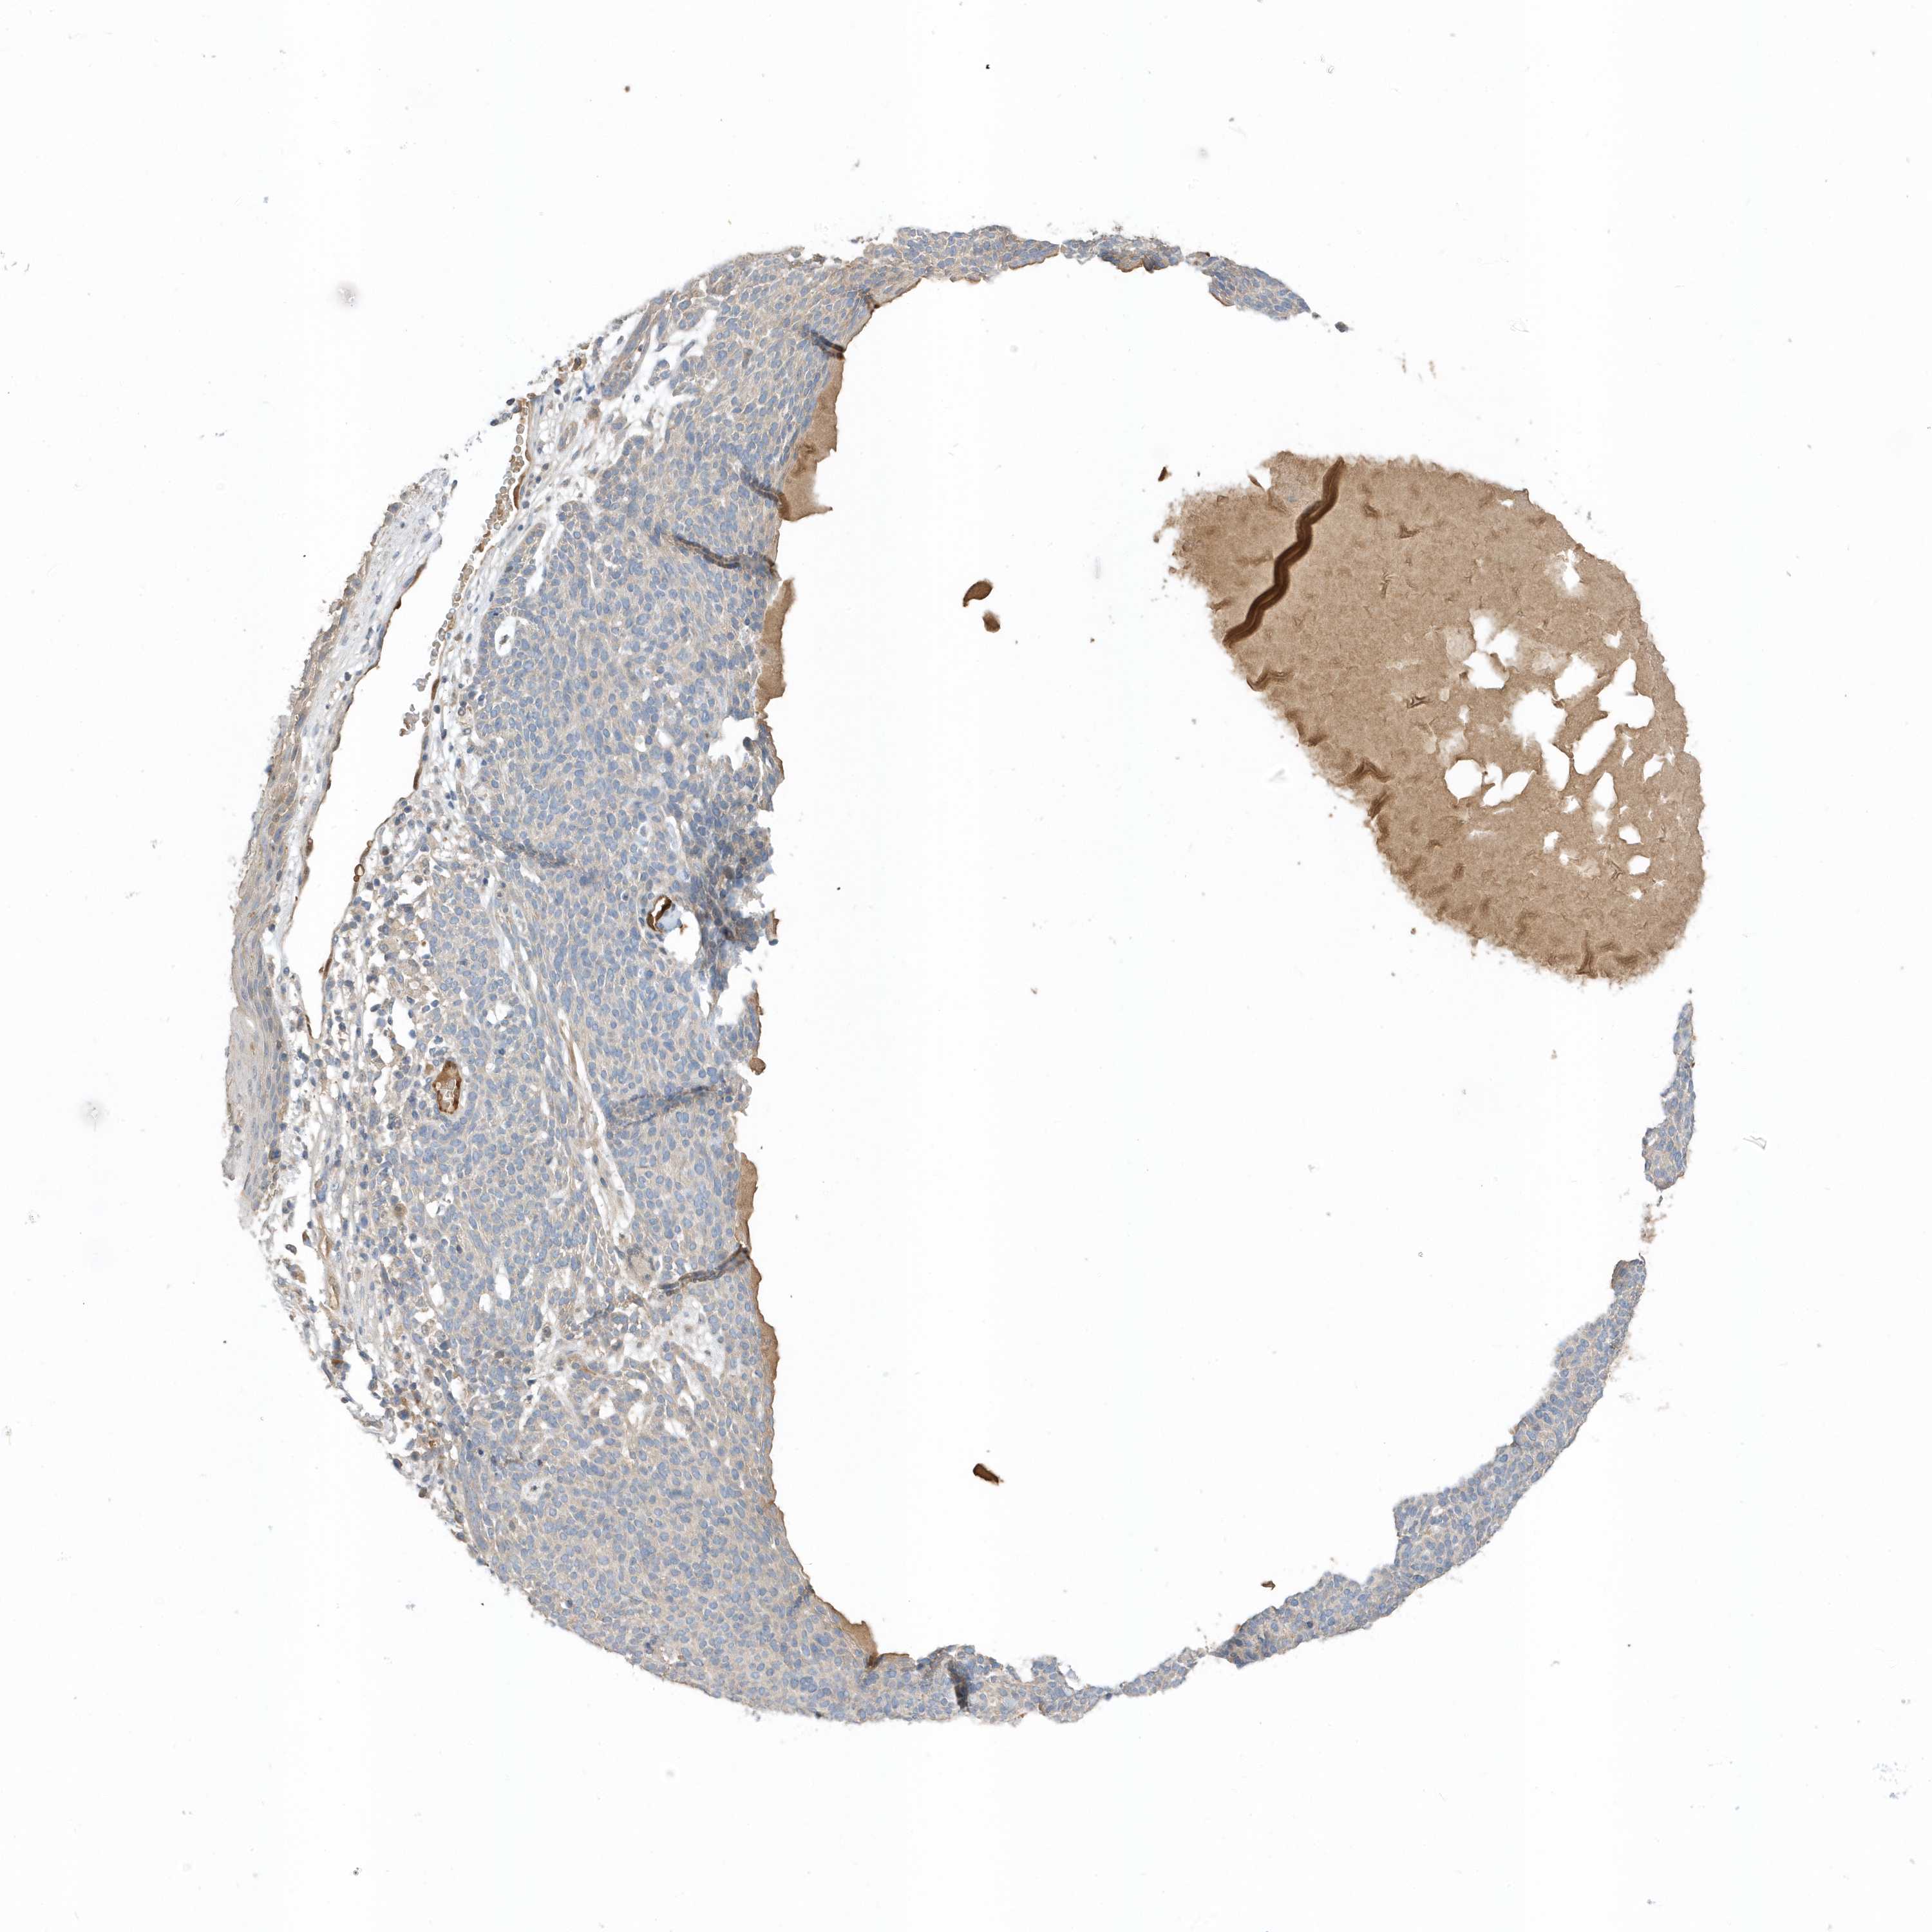

Basal cell and squamous cell cancer

SKIN CANCER - Protein expressioni

A mouse-over function shows sample information and annotation data. Click on an image to view it in a full screen mode. Samples can be filtered based on level of antibody staining by selecting one or several of the following categories: high, medium, low and not detected. The assay and annotation is described here.

Antibody stainingi

Antibody staining in the annotated cell types in the current human tissue is reported as not detected, low, medium, or high, based on conventional immunohistochemistry profiling in selected tissues. This score is based on the combination of the staining intensity and fraction of stained cells.

Each image is clickable and will lead to virtual microscopy that enables deeper exploration of all samples and also displays staining intensity scores, fraction scores and subcellular localization as well as patient and tissue information for each sample.

Antibody HPA035844

Antibody HPA035845

Staining

Medium

Moderate

75%-25%

Cytoplasmic/membranous

Squamous cell carcinoma, metastatic, NOS